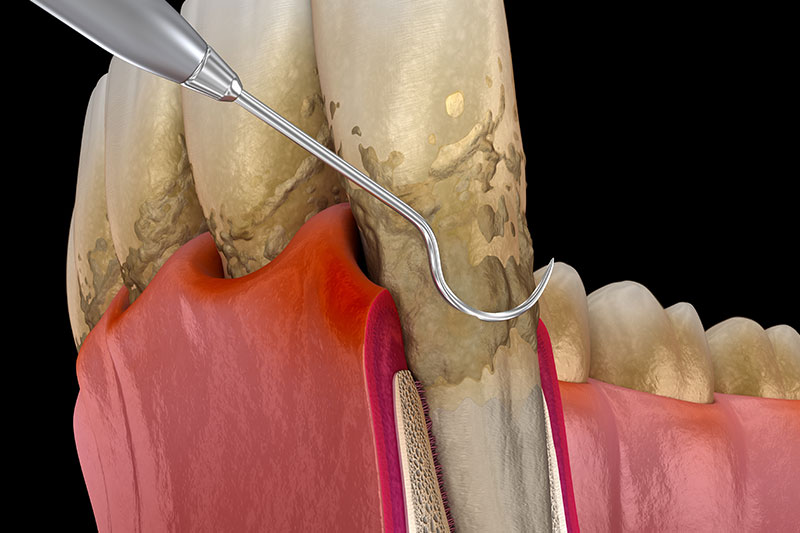

歯周外科、歯周組織再生療法

歯周基本治療では取り切れない場所にある歯石を取るために、歯茎を切開し、目に見える状態で処置をします。また適応であればエムドゲインやリグロスといった再生誘導材料を用いた歯周組織再生療法を行い、失った骨を再生させる治療を行います。